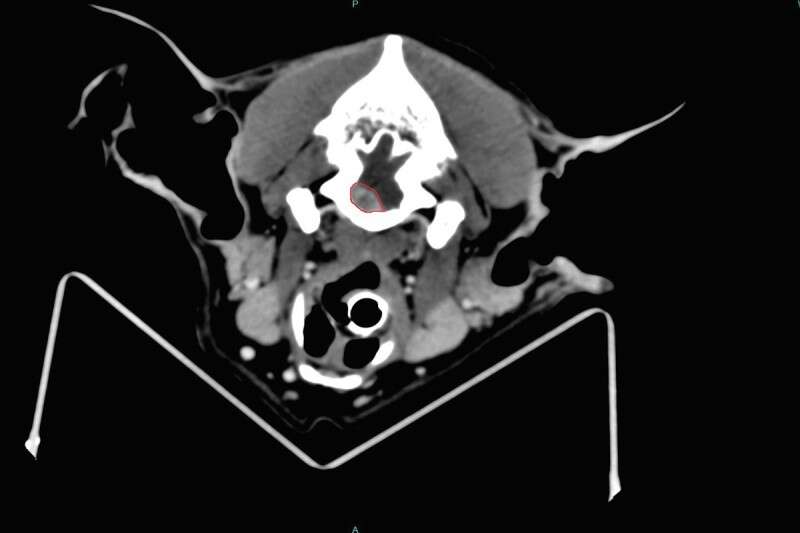

בסריקה נראה גידול גדול בגזע המוח (ככל הנראה מסוג מנינגיומה), ויואב וקרין נאלצו להכריע בתוך דקות על גורלו של עוזי: ניתוח או המתת חסד. "מכיוון שעוזי מבוגר התלבטנו מאוד", מבהיר יואב, "כימותרפיה בלבד לא היתה עוזרת, וידענו שמדובר בניתוח מורכב עם לא מעט סיכונים. אבל עד שהופיעו הסימנים הוא היה כלב חיוני מאוד והחלטנו לא לוותר עליו".

סריקת הסי.טי (הגידול באדום) // צילום:ביה"ח הווטרינרי האוניברסיטאי

כבר למחרת הוכנס עוזי לניתוח נוירוכירורגי להסרת הגידול בגזע המוח, שנחשב הראשון מסוגו בישראל, בשל מיקום הגידול והגישה הכירורגית שהכתיב. הוא בוצע על ידי פרופ' מרב שמיר וד"ר אורית חי, מומחיות בינלאומיות בנוירוכירורגיה וטרינרית (DECVN), ראשונות בתחומן בארץ, ומרצות בבית הספר לרפואה וטרינרית ע"ש קורט של האוניברסיטה העברית.